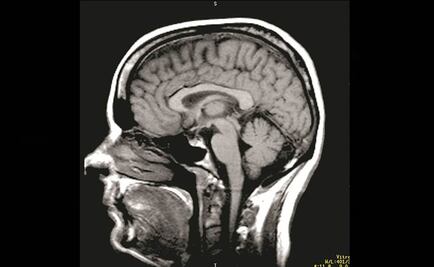

La operación tomó aproximadamente cuatro horas y contó con la participación de más de 10 especialistas

Tocó 'Yesterday', de los Beatles, durante horas mientras le extraían un tumor del cerebro